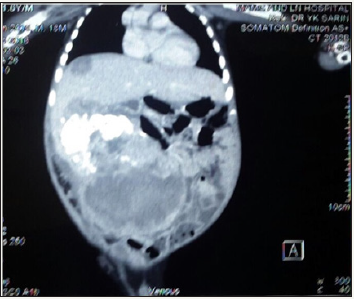

One and half-year-old boy was brought to us with a progressively increasing right-sided abdominal lump noticed since last 7 months. There was no other associated constitutional complaint. On examination, patient had stable vitals but gross pallor. Abdominal examination revealed a 15x15cm firm, immobile, non-tender mass with lobulated surface with ill-defined margins in the right lumbar, right hypochondriac, epigastric, umbilical and right iliac fossa regions. Liver margin could not be palpated separately. Rest of the systemic examination was normal. Investigations revealed severe anaemia with (Hb 3.4gm/dl). His renal and liver function tests were essentially normal with slight rise in AST level of 183 U/l. X-ray abdomen showed coarse calcifications in the area of the mass (Figure 1). Ultrasonography (USG) revealed a large solid lesion in right lumbar region with coarse calcification and vascularity; organ of origin could not be estimated accurately. Liver showed two target lesions in segment VII and VIII. Contrast enhanced computerised tomography (CECT) showed 11.5x9 cm predominantly exophytic, mildly enhancing mass lesion of having solid and cystic components having large calcifications; there were ill-defined planes between the mass and inferior margin of right lobe of liver (Figure 2 & 3). The mass was attenuation inferior vena cava posteriorly and displacing the portal vein superiorly, however both the vessels showed normal contrast opacification. The liver measured 12cm with a well-defined mildly enhancing lesion in superior segment of right lobe. Rest of the abdominal structures including spleen, bilateral kidneys, pancreas and thorax were normal. No abdominal lymphadenopathy or free fluid was noted.

Figure 2: Initial CECT image showing exophytic mass with target lesion in segment VII.

Figure 3: Initial CECT image showing extensive calcification.